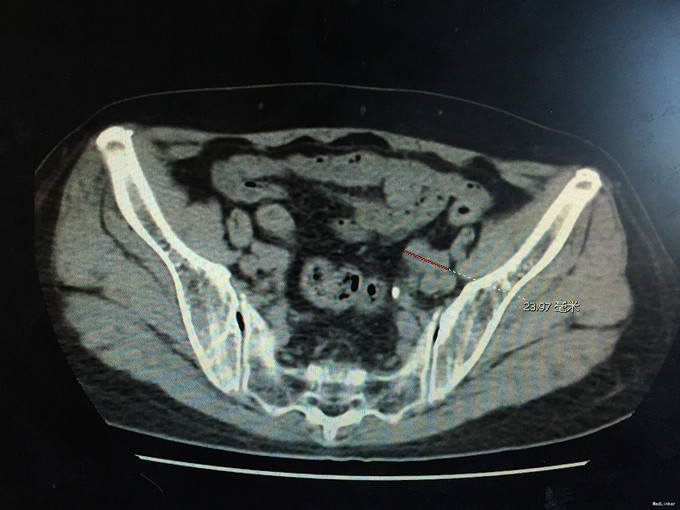

查体:无明显异常。 辅助检查:泌尿系CT如下图所示:左侧输尿管下段可见软组织密度影,其上输尿管、肾盂肾盏明显扩张、积水。腹、盆腔未见明显肿大淋巴结影。考虑输尿管下段软组织肿瘤性病变可能。

诊断:输尿管占位(输尿管肿瘤可能性大),肾盂输尿管扩张积水。 治疗:输尿管镜检查+病理活检,明确病理后再行下一步治疗方案。